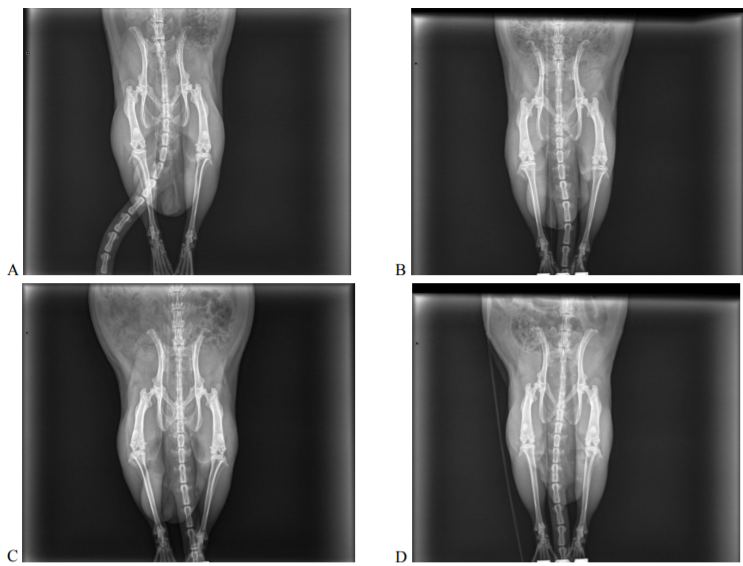

Taking into account the involvement of connective tissue in the systemic inflammatory response syndrome induced by the injected oil emulsion of heat-killed M. tuberculosis in the animals, the study of the musculoskeletal system enables evaluation of therapeutic effectiveness (Fig. 5).

Рис. 5. Ренгенологические снимки экспериментальных животных (А – негативный контроль; B – позитивный контроль; C, D – животные, получавшие смесь лимонной и янтарной кислот в минимальной и максимальной дозах)

Fig. 5. X-ray images of experimental animals (A – negative control; B – positive control; C and D – animals given a mixture of citric and succinic acids in minimum and maximum doses)

The articular system of the animals in the model group is characterized by cyst-like white spots in the heads of bones and their subchondral sclerosis. Uneven narrowing of joint spaces is typical of these animals. The warm-blooded animals that received antioxidant therapy in the diet are characterized by a decrease in dystrophic changes manifested by uneven narrowing of joint spaces and small cyst-like white spots; yet, the described changes can be reversible.

The animals of the negative control group had no visible pathological lesions.

that of the infectious etiology) is aimed at preventing oxidative stress and preserving high barrier properties of membranes impeding cell contamination. In this connection the antioxidant effect of a mixture of citric and succinic acids manifested by a dose-dependent decrease in the blood level of malondialdehyde in the experimental animals with M. tuberculosis-induced disorders increases the resistance of the body to the pathogen. This effect is based not only on the direct action of natural antioxidants inhibiting the oxidative process, but also on their stimulation of enzymes of the antioxidant defense system, as shown by catalase activation in treated animals (Fig. 3). The established high inverse correlation between the activity of SDH and level of hydroperoxides in plasma rxy = –0.90 also substantiates the regulatory role of organic acids in redox homeostasis: against the background of activation of cell respiration, stabilization of the release of primary products of oxidative destruction in membranes is noted. Evidence of an increase in the body’s resistance to damage through citric and succinic acids is the results of X-ray studies, which indicate a modification of the pathogenesis of autoimmune rheumatoid arthritis and the possibility of arresting pathomorphological changes even in the late stages of the disease.